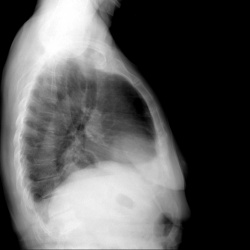

Здравствуйте. Буду признательна за ваши мнения. Пациент, 44 года, предъявляет жалобы на кашель, болеет 2-3 день, со слов. Нет ли патологии?